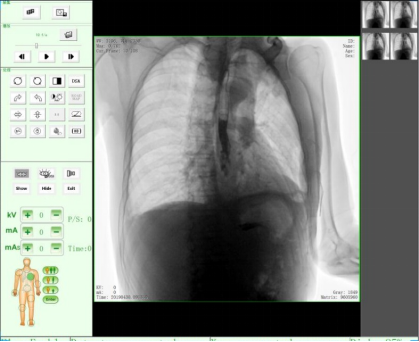

動態(tài)DR17*17英寸非晶硅動態(tài)平板探測器,透視像素達200萬,可實時顯示大幅面高清拍攝視野。適用于全身各部位攝影,包括常規(guī)攝影,如胸片、頸椎、腰椎、腹部、頭顱、四肢等,以及特殊攝影。

三、數(shù)字化透視

適用于全身各部位的透視檢查及輔助治療,如隱匿性肋骨骨折、胸透檢查、骨折復位、小兒腸套疊空氣灌腸等。同時具備多種幀率透視模式,影像更加流暢、準確。